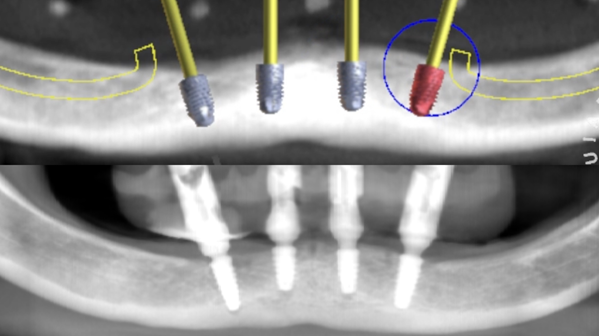

Atualmente, a tomografia computadorizada e softwares especializados (Exoplan, Nobel Guide, Simplant, BTI Scan II, Implant Viewer, Dental Slice, Blue Sky Plan) têm possibilitado o planejamento cirúrgico e protético virtual baseado na visualização tridimensional precisa do osso e sua relação com a futura prótese. Ao realizar o planejamento virtual é possível avaliar e mensurar a densidade óssea; selecionar tipo, tamanho e número de implantes; determinar a sua localização, inclinação e nível de profundidade em relação ao osso; analisar as características dos pilares intermediários e surgimento do parafuso de fixação da futura prótese; verificar o correto posicionamento dos anéis na guia cirúrgica e a localização ideal dos pinos de fixação, que são responsáveis pela estabilidade da guia na boca durante a cirurgia.1,8

Para o planejamento da prótese foram feitos exames da prótese removível que o paciente utilizava, além de exames tomográficos com materiais radiopacos para poder cruzar as telas. Os arquivos DICOM e STL foram convertidos para o formato Blue Sky Plan (Blue Sky Bio-Libertyville, Illinois, EUA), o que possibilitou a transformação das imagens tomográficas em objetos 3D. A partir deste recurso foi possível planejar a colocação dos implantes em sua posição ideal, guiado pelo computador.

O guia foi fixado após estabilização em oclusão com a prótese superior. Após a retirada do guia de oclusão, foi fixada a guia de fresagem e instalação dos implantes, que foram instalados com torques superiores a 32N, o que permitiu a captura imediata da prótese provisória através do pilar de titânio e resina de fluxo.